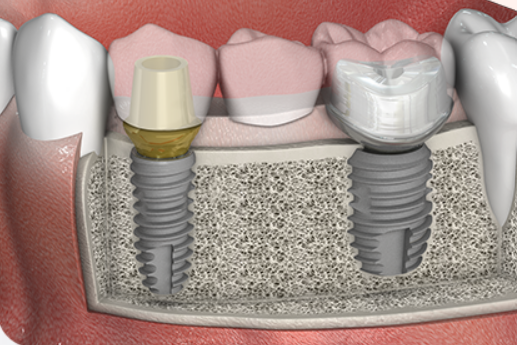

임플란트는 치과의 치료방법들 중 하나이며, 발치(이를뽑는 것)하여 인공치아를 이식하는 것을 말합니다. 기본적으로는 발치한 자리에 나사를 심고 이후 그 위에 이를 대체하는 인공치아를 덧 씌우는 것 입니다. 임플란트의 역사는 약 60년 정도 되었으며, 1980~1990년 부터 미국, 유럽등에 본격적으로 도입 되었습니다. 이 후 우리나라에는 2000년 초 부터 대중화가 이루어 졌습니다.

- (임플란트 시술과정) 시술할 이 발치 → 발치 한 자리에 임플란트 삽입 → 인공치아(보철물) 장착

- (임플란트 시술기간) 총 3~5개월 소요 / 임플란트 잇몸에 삽입 후 안정화 2~4개월 + 인공치아(보철물) 작업 1개월